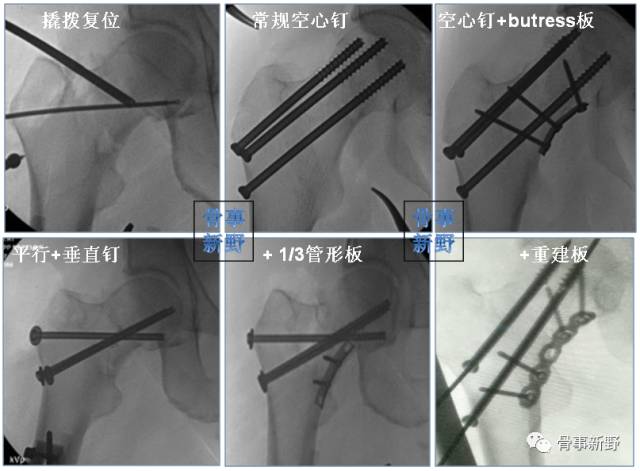

股骨颈骨折的medial buttress

垂直型股骨颈骨折(Pauwels III型)常因垂直剪力大、常规三枚平行空心钉固定易致内固定失败,单纯空心钉+第四枚垂直螺钉或medial buttress 钢板可起到对抗垂直剪力的防滑、支撑作用。

股骨颈内侧的防滑、支撑(Medial buttress)

Medial buttress是指在股骨颈骨折解剖复位、平行拉力钉常规加压后,于股骨颈下内侧、放置一块3-4孔三分之一管型钢板、重建钢板或其它微型钢板,在紧靠骨折尖下方打入一枚穿过双层皮质的防滑螺钉(Buttress screw),再在远、近侧根据情况打入第二枚或更多螺钉。这样,通过钢板的支撑作用可将骨折断端间的垂直剪切力转化为利于骨折愈合的压应力。这种应力转化有利于预防垂直型不稳定股骨颈骨折常见的内翻塌陷及不愈合并发症[Mir 2015]。